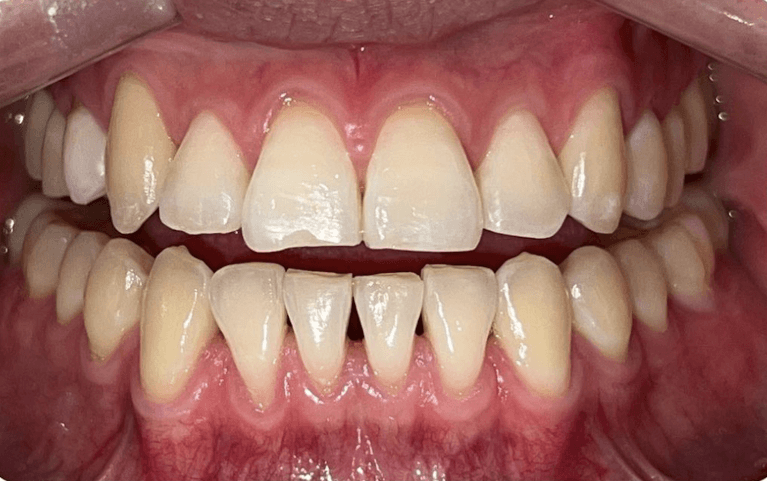

Before and after with Invisalign orthodontic treatment. Pictures taken with different phones at different setting. Used total of 27 aligners/trays. Treatment time 13.5 months